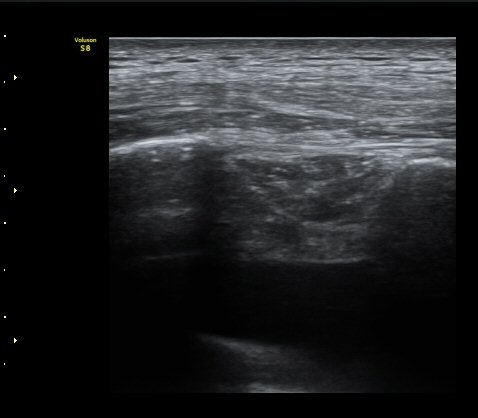

±¤¹è±Ù ½ÉºÎ¿¡ °¥ºñ»À»çÀ̱ÙÀÌ °üÂûµÇ°í °¥ºñ»À»çÀٰ̱ú Æó»çÀÌ¿¡ ¼ö¾×Àú·ù°¡

°üÂûµÊ(intercostal muscle deep to latissimus dorsi, fluid accumulation between intercostal muscle and lung)   »çÁø 4

°¥ºñ»À »çÀÌ¿¡ °¥ºñ»À»çÀ̱ÙÀÌ °üÂûµÇ°í °¥ºñ»À»çÀٰ̱ú Æó»çÀÌ¿¡ ¼ö¾×Àú·ù°¡

°üÂûµÊ (intercostal muscle between ribs,  fluid accumulation between intercostal muscle and lung) »çÁø 5    µ¿¿µ»ó